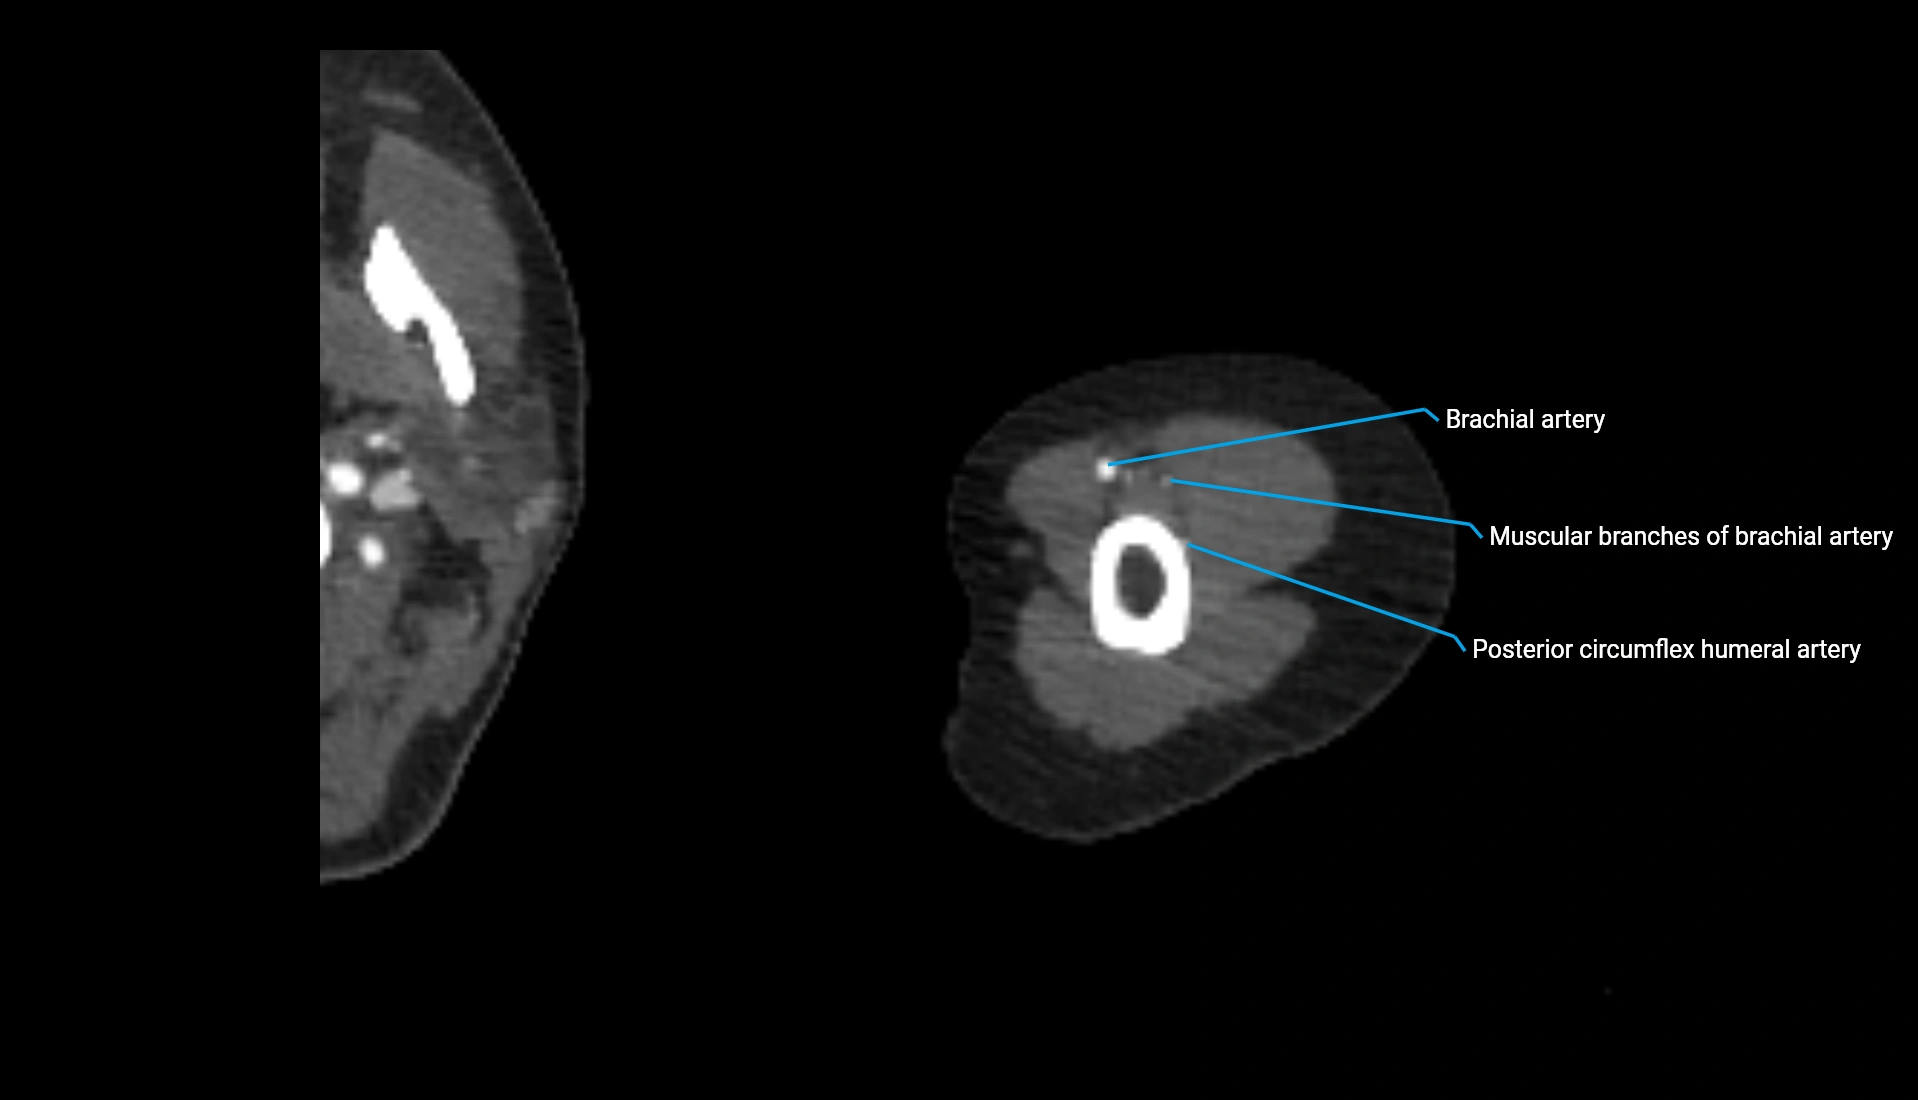

CT Appearance

Non-Contrast CT:

• Cortex: High-density, sharply defined

• Subchondral bone: Dense cancellous matrix

• Articular surface: Smooth concave contour articulating with the capitellum

• Excellent for evaluating bone integrity, alignment, and subtle fractures